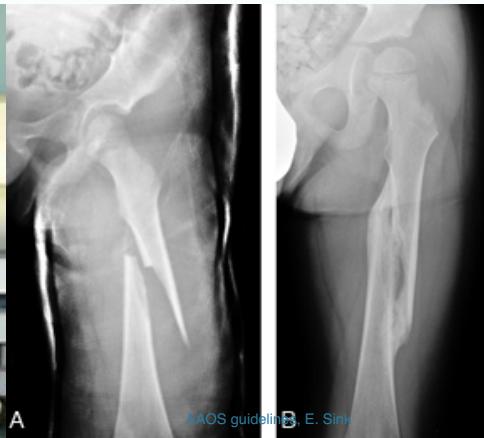

Intertrochanteric Fractures

Characteristics

- Extra-capsular

- Good blood supply

- Heal well

- Low risk for avascular necrosis

Treatment

- Usually operative

- Dynamic hip screw (DHS)

- Proximal femoral nail